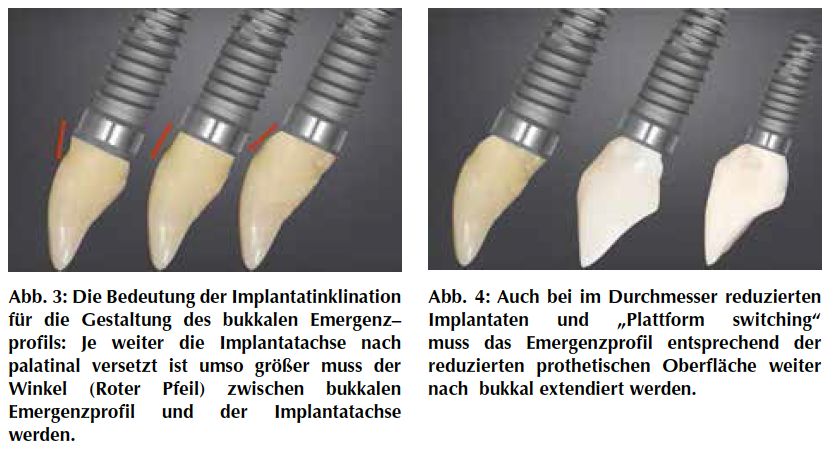

Die Positionierung der Implantatachse in der Relation zum Kieferkamm hat einen wesentlichen Bezug zum prospektiven Emergenzprofil der implantatgetragenen Versorgung. Je weiter die Implantatachse nach palatinal verschoben ist, umso größer muss der Winkel zwischen Implantatachse und bukkalem Emergenzprofil werden. Durchmesserreduzierte Implantate oder „Platformswitching“ haben einen ähnlichen Einfluss auf die Gestaltung des Emergenzprofils.